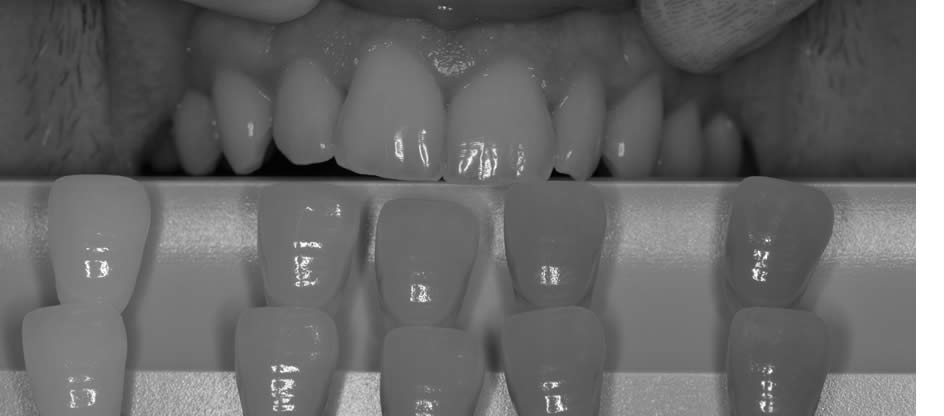

Un passage en noir et blanc sera un excellent moyen de contrôler la luminosité.

Il est aussi possible de jouer sur les contrastes pour mettre en avant les zones de translucidité.

Le système de lumière polarisée Polar Eyes complète avantageusement les informations transmises au prothésiste. Cette technique va permettre de s’affranchir des reflets de l’émail et ainsi donner un maximum d’informations sur les répartitions des masses dentaires.

Le principe est celui d’une lumière polarisée croisée émise par les flashs et recaptée par l’objectif.